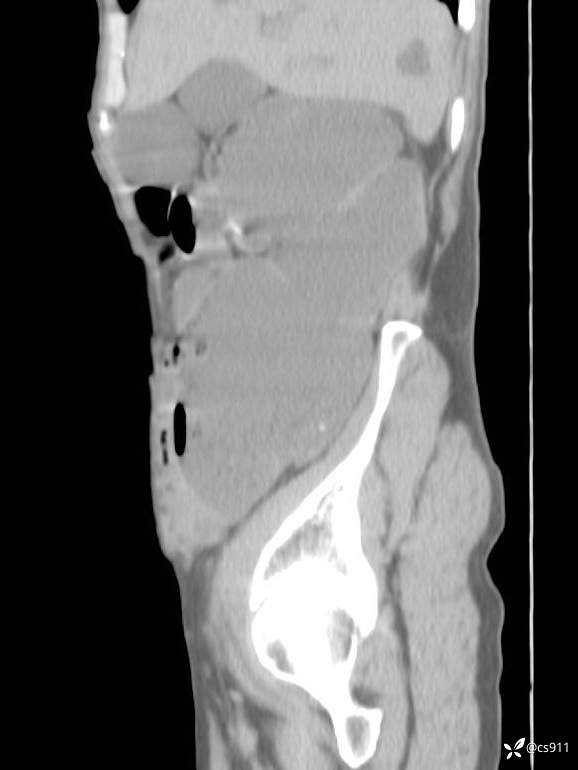

急腹症之急诊CT,原因?答案公布

男,77岁,腹痛、腹胀伴恶心呕吐1天。呕吐胃内容物,非喷射性呕吐,有咖啡色样胃内容物,诉有胃穿孔病史。查体:全腹平,下腹部压痛,全腹无反跳痛,叩诊呈浊音,移动性浊音阴性,肠鸣音减弱,1-2次/分。肛检:直肠未扪及明显肿物,可触及大量粪块。

T 36.6℃ P 80次/分 R 26次/分 BP 100/60mmHg

白细胞(WBC) H 14.55 10e9/L 4-10

红细胞(RBC) 4.58 10e12/L 4.3-5.8

中性粒细胞百分率(NEUT%) H 85.7 % 40-75

血淀粉酶(AMY) HH 1859 U/L 35-135

癌胚抗原(CEA) H 27.44 ng/ml 0-5

呕吐物 潜血试验 * 阳性 阴性

患者轮椅入室检查神志清楚, 能配合摆位和呼吸